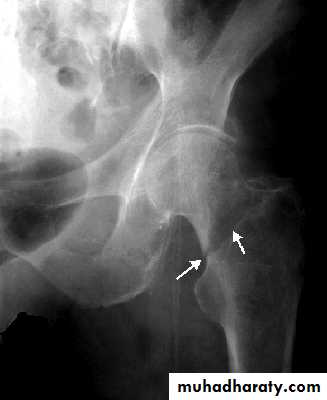

GRADE 3

The femoral head tilted out of position and the trabecular marking are not in line with those of innominate bone.

Lower limbs